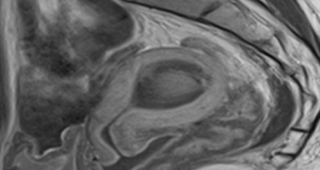

자궁선근증 하이푸 시술 후 1년 임신과 출산 사례입니다.6.5 cm 자궁선근증 하이푸 치료시간은 96분이 소요되었습니다. (Adenomyosis Hifu treatment time 96min)아래의 MRI 사진은 자...